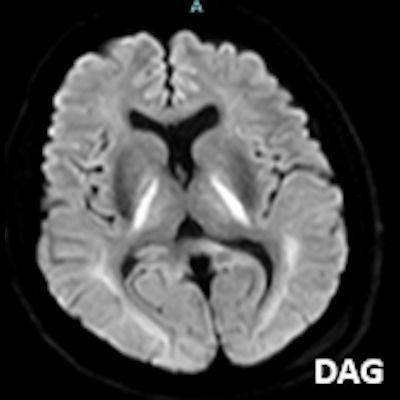

- A) Bilateral serebral kortekste (oklar) ve bazal ganglionlarda (oklar) yaygın DAG hiperintens, ADC hipointens difüzyon kısıtlamaları görülüyor.

- B) 9 gün sonraki difüzyon MR incelemede kortikal ve bazal ganglionlardaki difüzyon kısıtlamalarının gerilediği, bilateral serebral beyaz cevherde (oklar) ve internal kapsül arka bacağı- kortikospinal trakt boyunca (oklar) yaygın DAG hiperintens, ADC hipointens difüzyon kısıtlamalarının geliştiği izleniyor.